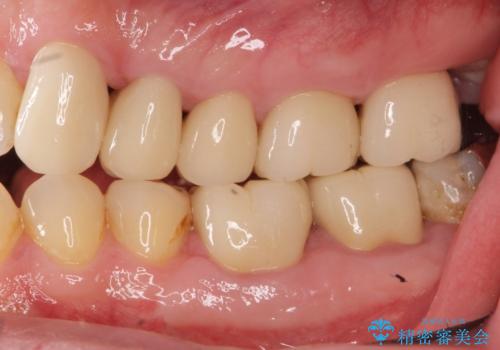

銀歯・虫歯・治療途中の歯を治していきたい